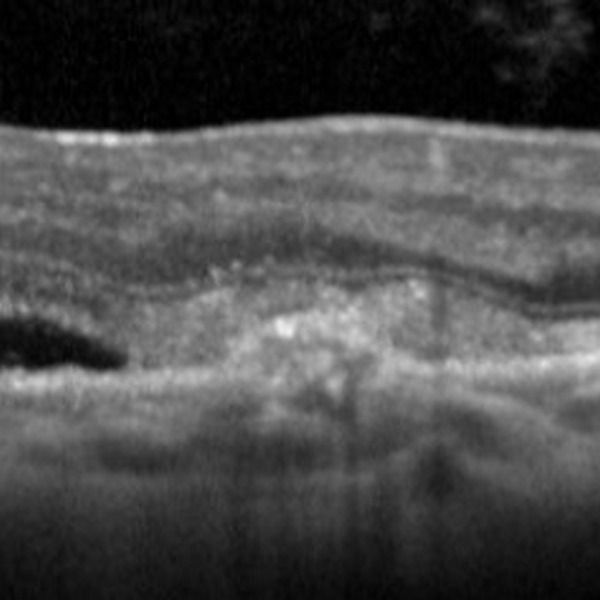

La réalisation d’une tomographie par cohérence optique OCT est rapide, indolore, non invasive et permet d’obtenir des résultats reproductibles. L’OCT est donc devenu un examen de routine incontournable dans le diagnostic et suivi des lésions liées à la DMLA. Les technologies récentes permettent de visualiser avec précision l’existence de ces anomalies, de préciser également leurs topographies et même de les quantifier.

Savoir reconnaître les différentes formes de la DMLA en OCT

Analyser le suivi des patients DMLA en OCT